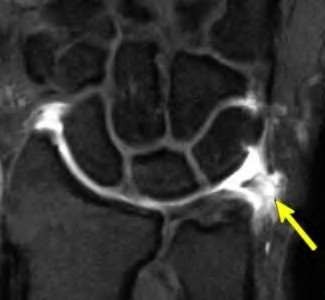

Contrast enhanced MRA of the wrist is typically used to diagnose hypothenar hammer syndrome or other vascular abnormalities.

A 20-year-old park ranger trips and falls onto his right wrist with the wrist in extension and pronation. The local urgent care orders both radiographs and a CT, which you review and determine to be normal. The patient complains of ulnar-sided wrist pain. On exam, his tenderness is localized to the fovea. Ulnar deviation also causes him pain. There is no snapping sensation with wrist supination, flexion, and ulnar deviation. He otherwise has 5/5 strength to his first dorsal interosseous muscle with 4mm static two-point discrimination on the ulnar side of the 4th digit. Which of the following injuries is most likely responsible for his symptoms and exam?